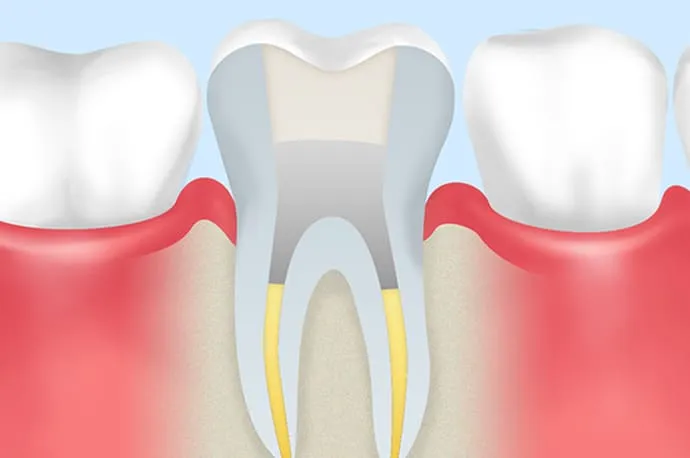

虫歯が重度に進行すると、虫歯菌が歯の神経まで感染し、歯の内部にある神経を取り除く必要が出てくることがあります。

根管治療とは、文字通り「歯の神経が入っている根の管(根管)」に対して行う治療です。 もし根管治療を行わずに放置してしまうと、細菌が歯の根の先にたまり、やがて根の先が化膿してしまいます。その結果、強い痛みが出たり、歯ぐきや頬が腫れたりすることもあります。

まだ死んでいない歯の神経を取り除く処置を抜髄といいます。虫歯や歯の破折が原因で細菌が歯の神経まで到達し、炎症を起こしている状態(歯髄炎)がこれにあたります。